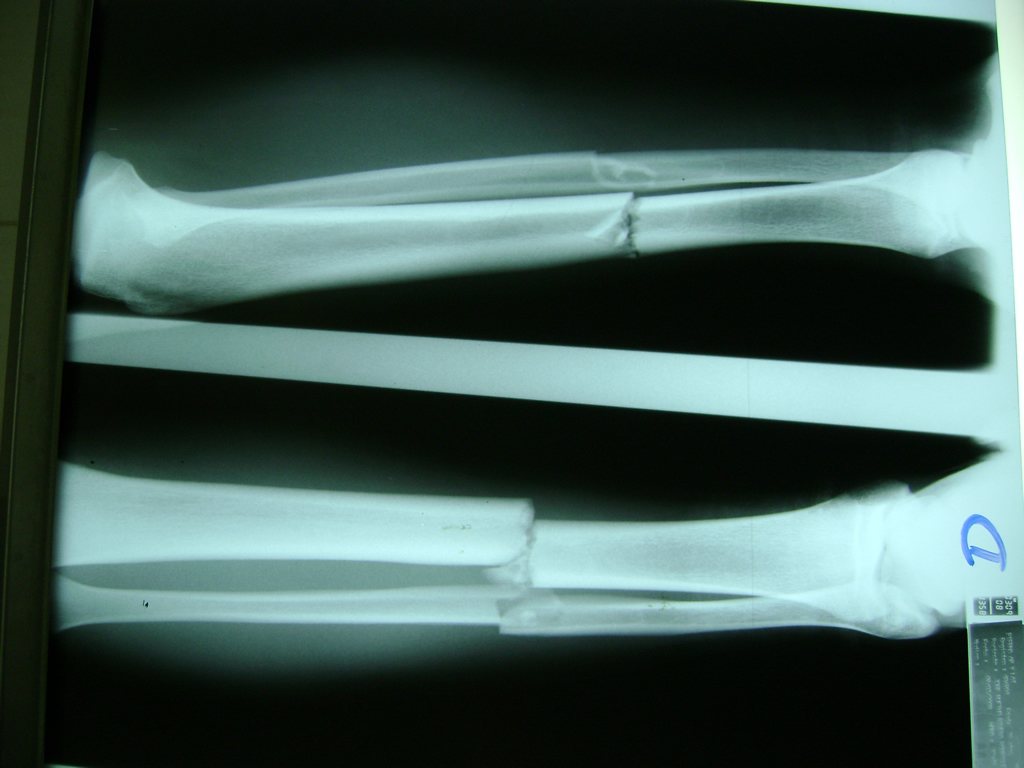

Fémur - Perone y Tibia

Aunque cada uno de estos huesos puede fracturarse por separado, normalmente la rotura es una lesión que se produce de forma conjunta

La mayor parte de las roturas implican a la parte proximal del hueso (parte del hueso próximo a la rodilla) o a la parte distal (parte del hueso cerca del tobillo).

Debido a la fina cobertura de piel que recubre la tibia y el peroné, las fracturas generalmente son abiertas, es decir, el hueso roto rasga la piel, atravesándola. Las fracturas de tibia y peroné generalmente se producen por un fuerte impacto o torsión.